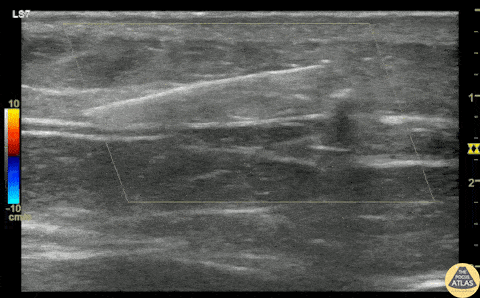

A teenaged female presented with a retained foreign body after she laid on top of a broken glass hand mirror. She removed one glass shard prior to ED arrival but one piece remained that she could feel under her skin. On exam, there was a tiny laceration but a 1-2 cm palpable foreign body under the skin. Blind foreign body removal under local anesthesia was not successful, so POCUS was employed to aid in visualization of the foreign body. A linear hyperechoic foreign body is seen in this clip, and was able to be removed under real-time US guidance using forceps and a hemostat. Repeat POCUS showed complete removal of the foreign body, and the patient was able to be discharged. Dr. Keren Eyal, PGY1, Children’s Hospital Colorado Pediatric Residency Dr. Michael Heffler, PGY4, Denver Health Residency in Emergency Medicine Dr. Nhu-Nguyen Le, Fellow, Denver Health Ultrasound Fellowship